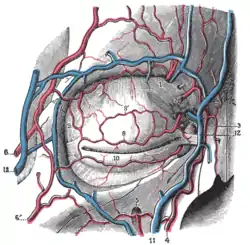

Blood supply

In humans, the eyelids are supplied with blood by two arches on each upper and lower lid. The arches are formed by anastomoses of the lateral palpebral arteries and medial palpebral arteries, branching off from the lacrimal artery and ophthalmic artery, respectively.

The lacrimal apparatus. Right side Extrinsic eye muscle. Nerves of orbita. Deep dissection

Extrinsic eye muscle. Nerves of orbita. Deep dissection